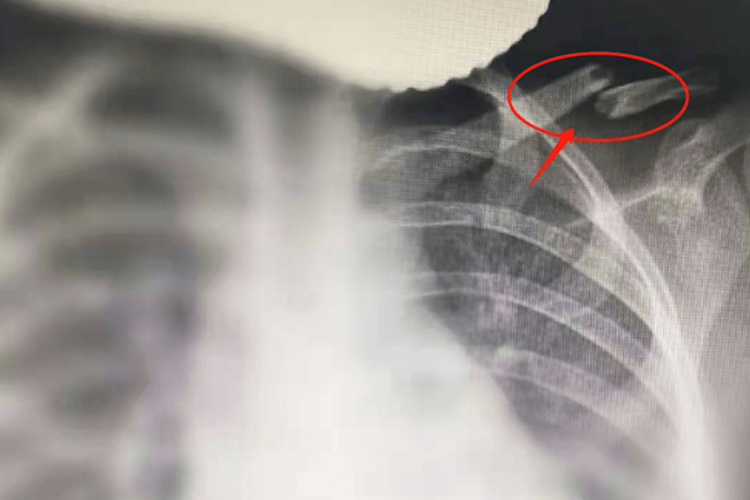

胸部的正位X线平片可清晰地显示左锁骨骨折断端的位置。